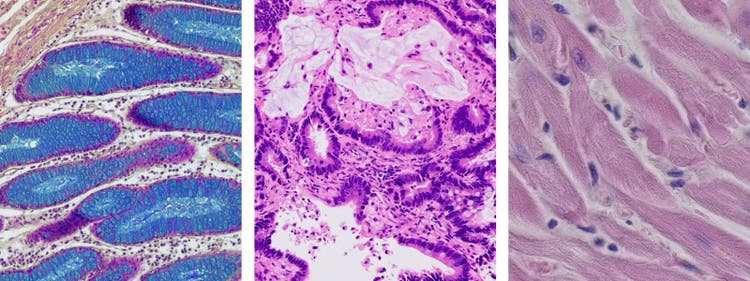

명시야 현미경법은 세포 및 조직부터 미네랄과 섬유에 이르기까지 다양한 샘플을 관찰하는 데 사용할 수 있습니다. 여러 연구 분야 및 산업 분야에서 다양한 용도로 사용할 수 있는 도구입니다.